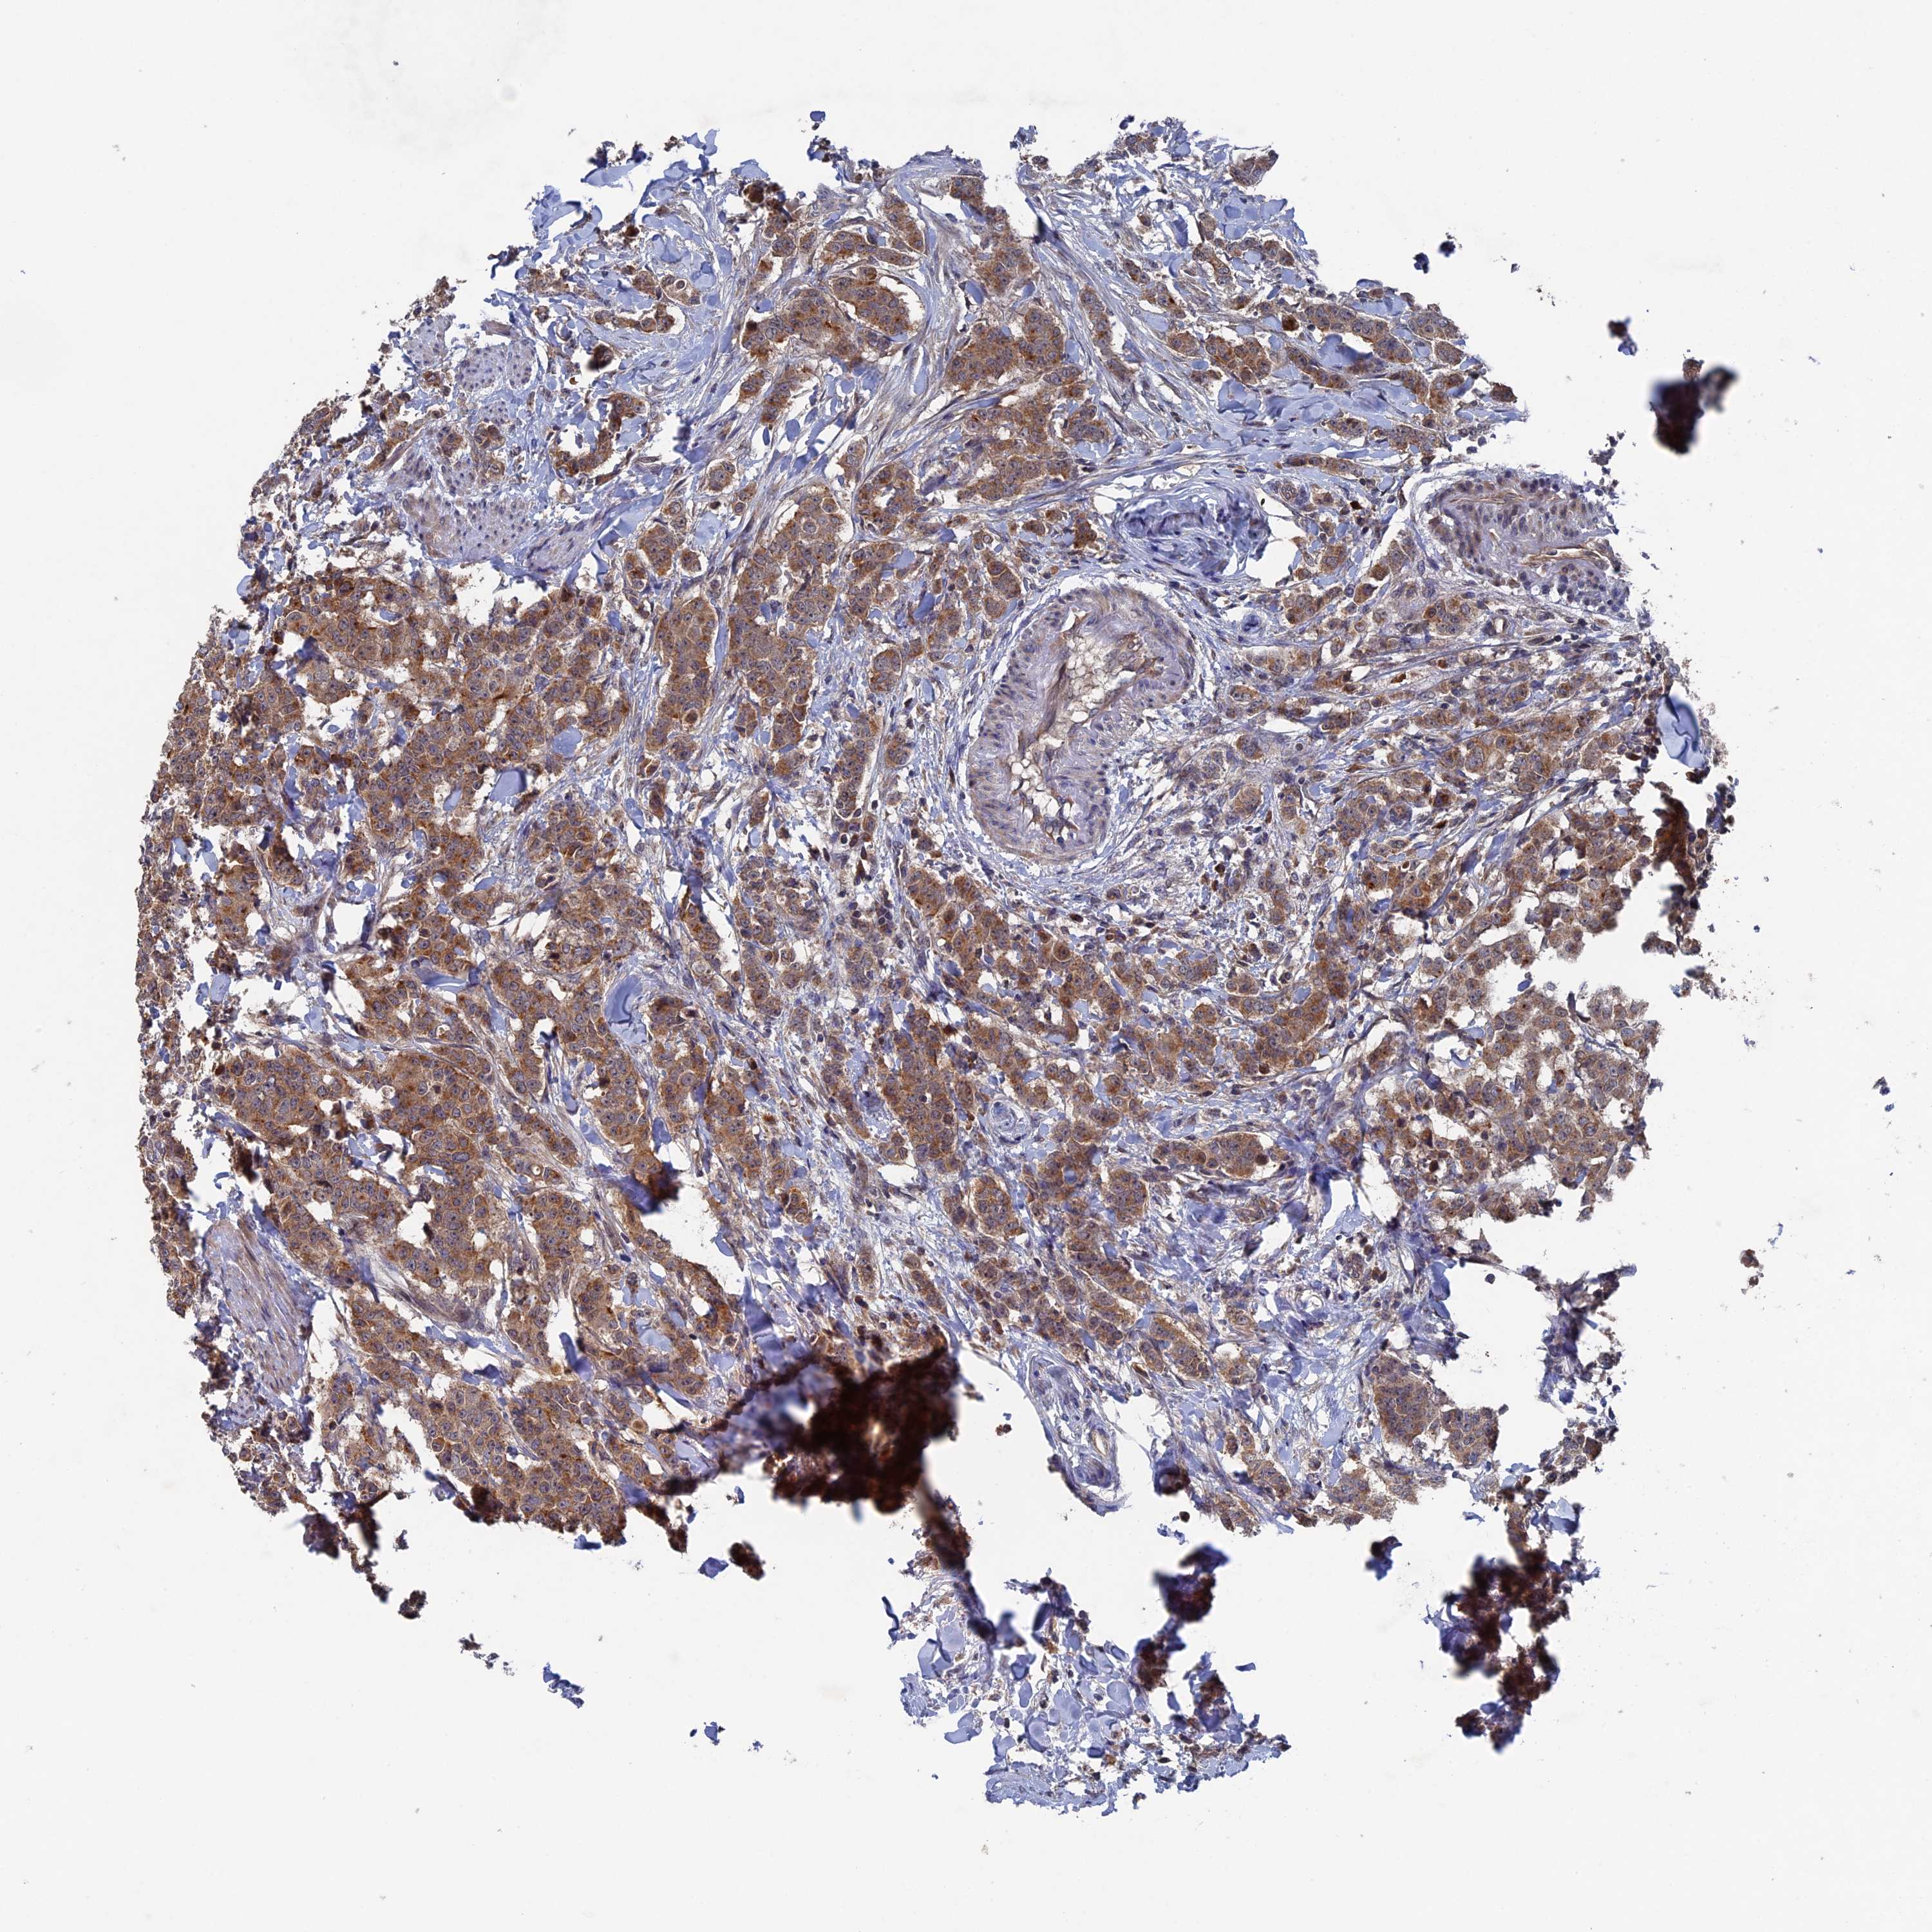

BRCA TCGA BRCA VALIDATION PROTEIN EXPRESSION